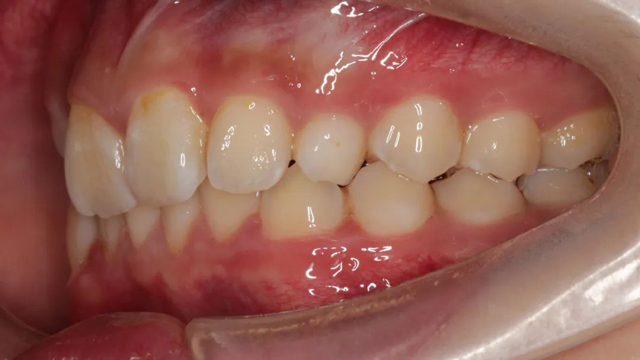

2024年9月(矯正結(jié)束后口內(nèi)照)

“隱形矯正一般2-3月復(fù)診一次,從節(jié)約時(shí)間來(lái)說(shuō)很受家長(zhǎng)青睞,但前提是小朋友要有很好的依從性,這是獲得滿意效果的前提。案例中的這個(gè)小朋友和家長(zhǎng)與醫(yī)生的配合度非常高,這也是我們能治療成功的必要因素。”